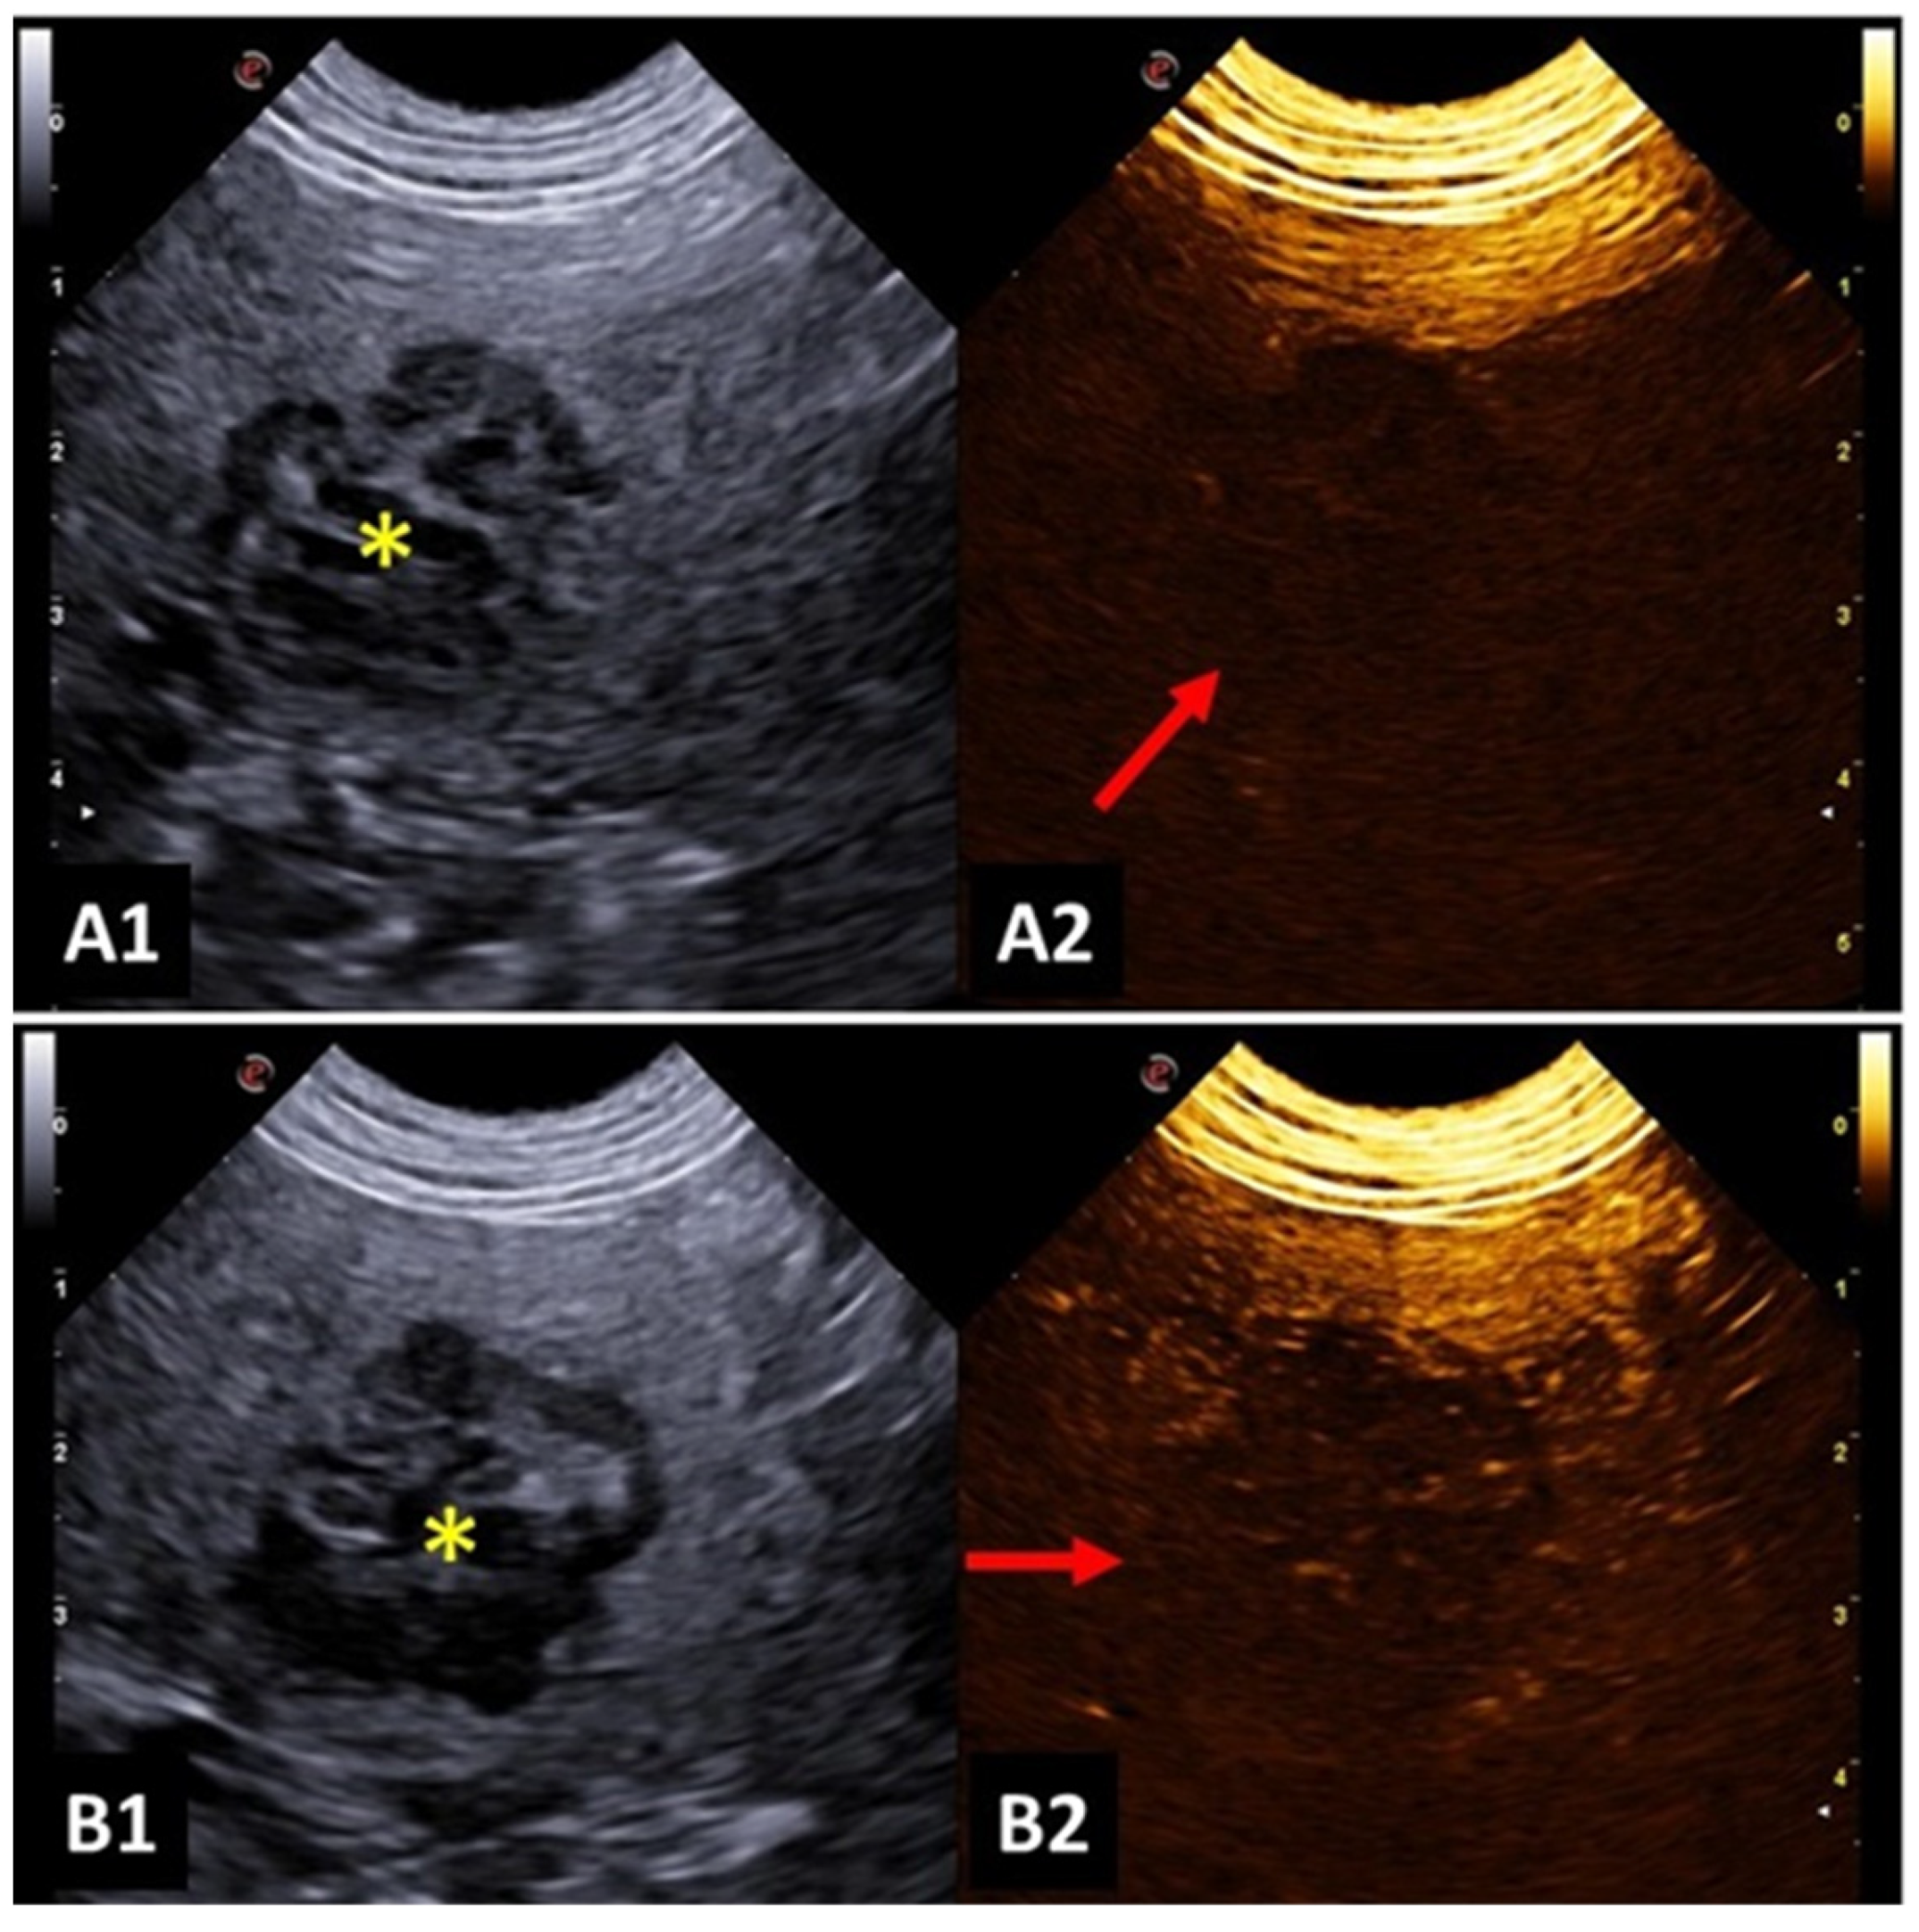

4.5. Spleen

- Rossi, F.; Leone, V.F.; Vignoli, M.; Laddaga, E.; Terragni, R. Use of contrast-enhanced ultrasound for characterization of focal splenic lesions. Vet. Radiol. Ultrasound 2008, 49, 154–164. [Google Scholar] [CrossRef]

- Taeymans, O.; Penninck, D. Contrast enhanced sonographic assessment of feeding vessels as a discriminator between malignant vs. benign focal splenic lesions. Vet. Radiol. Ultrasound 2011, 52, 457–461. [Google Scholar] [CrossRef]